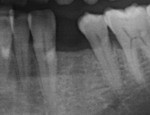

种植牙一例

种植前后照片对比